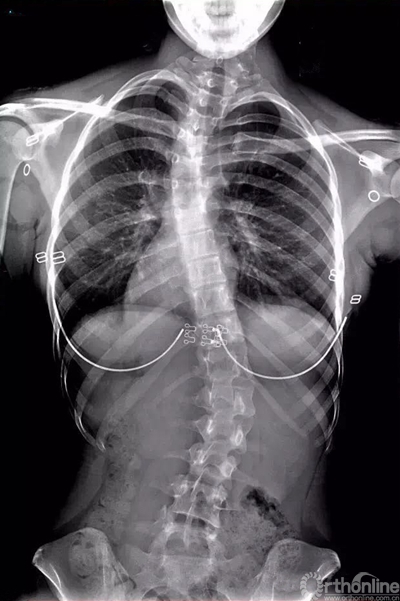

其实,对于脊柱侧弯的早期诊断并不难。家长可带孩子前往医院拍摄一张清晰的脊柱全长站立位X线片。如应用Cobb角法测量脊柱侧方弯曲角度大于10°则为脊柱侧弯。然而,尽量不要躺着拍摄这类脊柱X线片。这样会在一定程度上掩盖患者的真实病情,尤其对于脊柱柔韧性较好的轻度患者,拍摄出的效果可能会表现为“正常”。